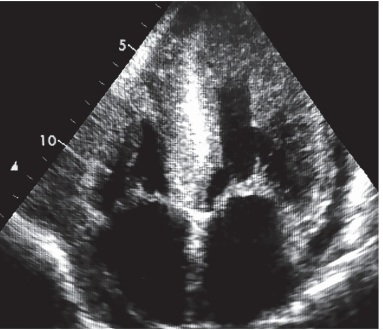

Mulher de 79 anos é encaminhada para realização de ecocardiograma transtorácico com vistas a

esclarecimento de padrão de cardiomiopatia dilatada (ICFEr) associada a proteinúria nefrótica e discretas

equimoses peripalpebrais. O exame complementar revela um brilho intenso no septo interventricular

(fi gura abaixo) associado ao padrão “apical sparing”.

Disponível em: https://portal.afya.com.br/cardiologia/o-ecocardiograma-na-amiloidose-quais-os-achados-tipicos. Acesso em: 12 jan. 2026.